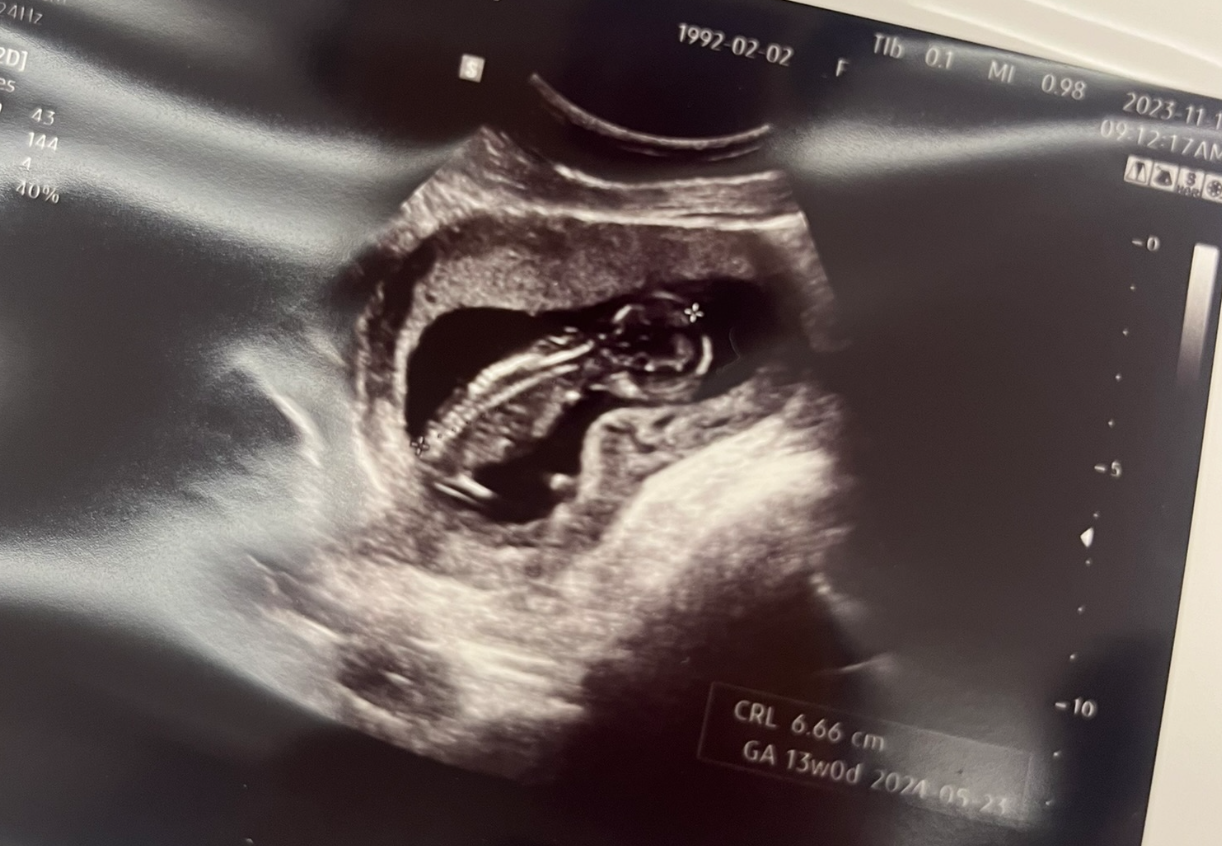

12주차 초음파 사진을 보니 우리 띠용이도 어엿한 사람의 모습을 갖추고 있었다.

너도 열심히 크고있구나, 아빠도 열심히 노력한단다...T^T

12주차에 열심히 엄마 양수에서 헤엄치는 모습을 보고 있자니, 웃음이 절로 나온다.

(이제 나도 아빤가 보다, 생명의 신기함을 느낀다.)

와이프 말로는 애기가 잘 움직이지 않아, 사탕을 먹었더니 그 뒤로 잘 움직인다고 얘기를 전해들었다.